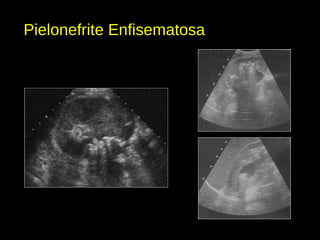

Pielonefrite Enfisematosa

• Gás no sistema coletor ou no rim.

• Pode ser secundária a manipulações, fístulas com o sistema digestivo ou por

infecção urinária por patógenos gram-negativos.

• > DM.

• Achados ao US:

- Gás nas vias coletoras, pelve, parênquima renal e até em coleções perirrenais

(abscessos).

- Formações hiperecogênicas amorfas, com reverberação posterior (“sombra

suja”).

- Podem formar nível gás-líquido.